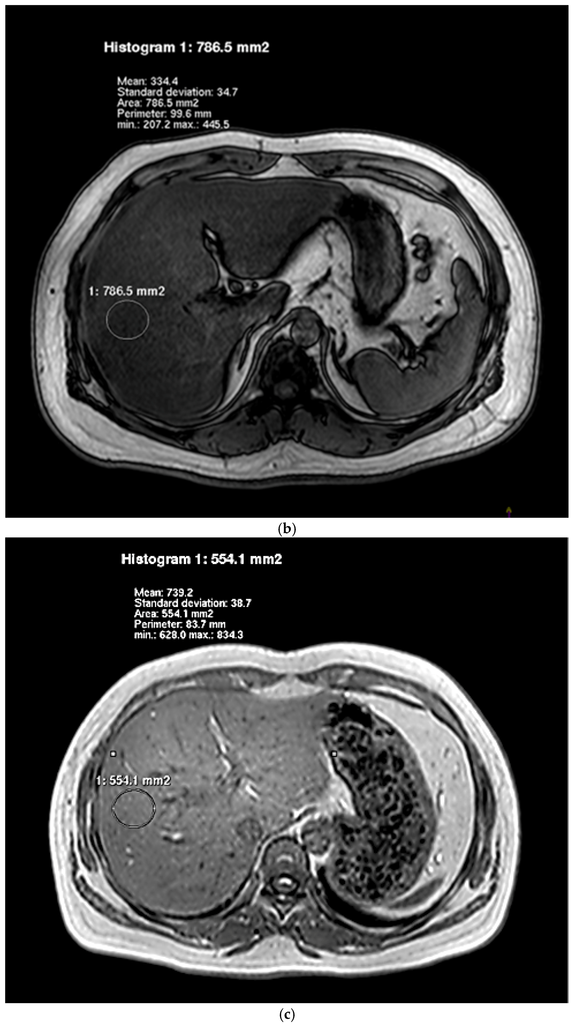

Associations between Dietary Nutrient Intakes and Hepatic Lipid Contents in NAFLD Patients Quantified by 1H-MRS and Dual-Echo MRI

by Yipeng Cheng, Kewei Zhang, Yang Chen, Yanchuan Li, Yuzheng Li, Kuang Fu and Rennan Feng

Nutrients 2016, 8(9), 527; https://doi.org/10.3390/nu8090527 - 27 Aug 2016

Dietary habits are crucial in the progression of hepatic lipid accumulation and nonalcoholic fatty liver disease (NAFLD). However, there are limited studies using 1H-magnetic resonance spectroscopy (1H-MRS) and dual-echo in-phase and out-phase magnetic resonance spectroscopy imaging (dual-echo MRI) to assess [...] Read more.

Dietary habits are crucial in the progression of hepatic lipid accumulation and nonalcoholic fatty liver disease (NAFLD). However, there are limited studies using 1H-magnetic resonance spectroscopy (1H-MRS) and dual-echo in-phase and out-phase magnetic resonance spectroscopy imaging (dual-echo MRI) to assess the effects of dietary nutrient intakes on hepatic lipid contents. In the present study, we recruited 36 female adults (NAFLD:control = 19:17) to receive questionnaires and medical examinations, including dietary intakes, anthropometric and biochemical measurements, and 1H-MRS and dual-echo MRI examinations. NAFLD patients were found to consume diets higher in energy, protein, fat, saturated fatty acid (SFA), and polyunsaturated fatty acid (PUFA). Total energy intake was positively associated with hepatic fat fraction (HFF) and intrahepatic lipid (IHL) after adjustment for age and body-mass index (BMI) (HFF: β = 0.24, p = 0.02; IHL: β = 0.38, p = 0.02). Total fat intake was positively associated with HFF and IHL after adjustment for age, BMI and total energy intake (HFF: β = 0.36, p = 0.03; IHL: β = 0.42, p = 0.01). SFA intake was positively associated with HFF and IHL after adjustments (HFF: β = 0.45, p = 0.003; IHL: β = 1.16, p = 0.03). In conclusion, hepatic fat content was associated with high energy, high fat and high SFA intakes, quantified by 1H-MRS and dual-echo MRI in our population. Our findings are useful to provide dietary targets to prevent the hepatic lipid accumulation and NAFLD. Full article